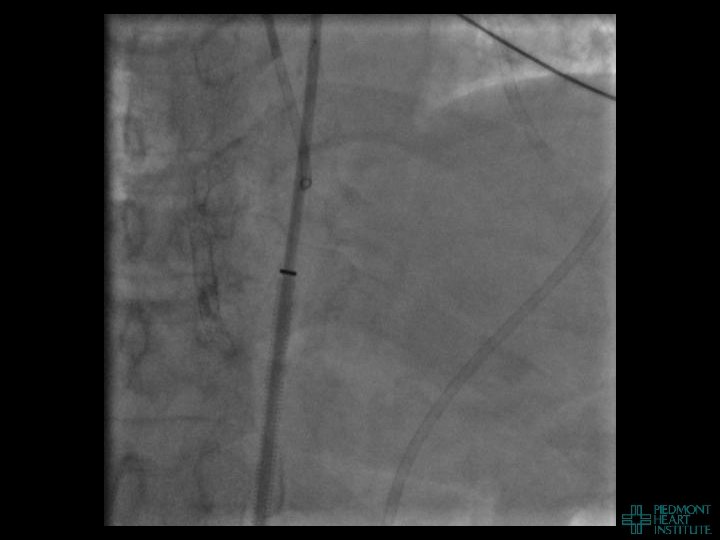

Case Example 4